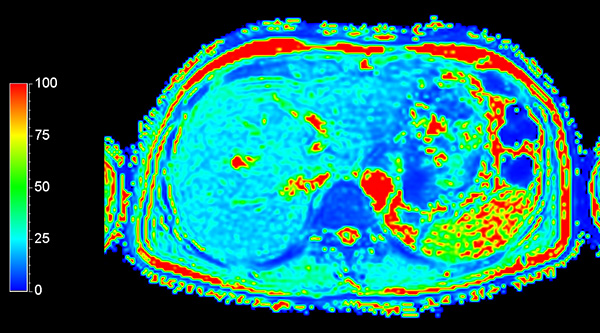

Axial mDIXON Quant (Fat Fraction)

Axial mDIXON Quant (T2*)